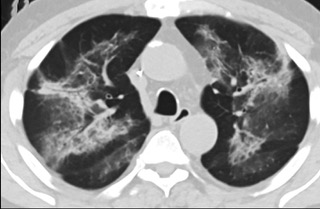

疑點一,電子煙患者的CT影像和臨床表現并不具有特異性。所謂美國電子肺炎患者,其實是對沒有其他合理診斷證據、吸食電子煙肺炎患者的統稱。這些患者在病發前90天內吸食了電子煙,尤其值得注意的是,部分患者的CT影像特征和臨床表現與病毒性肺炎患者極其相似。

中、下肺軸位CT平掃顯示毛玻璃樣混濁伴胸膜下保留。(同一病人CT影像)

中、下肺軸位CT平掃顯示毛玻璃樣混濁伴胸膜下保留(箭頭)。(同一病人CT影像)

疑點二,中國科研工作者從60篇研究論文中篩選出142位電子煙肺炎患者的250張影像圖片,邀請3位放射科權威專家,對上述全部影像圖片、相關病人臨床信息以及文獻原文進行了仔細全面研究與審查,又有了新的發現。